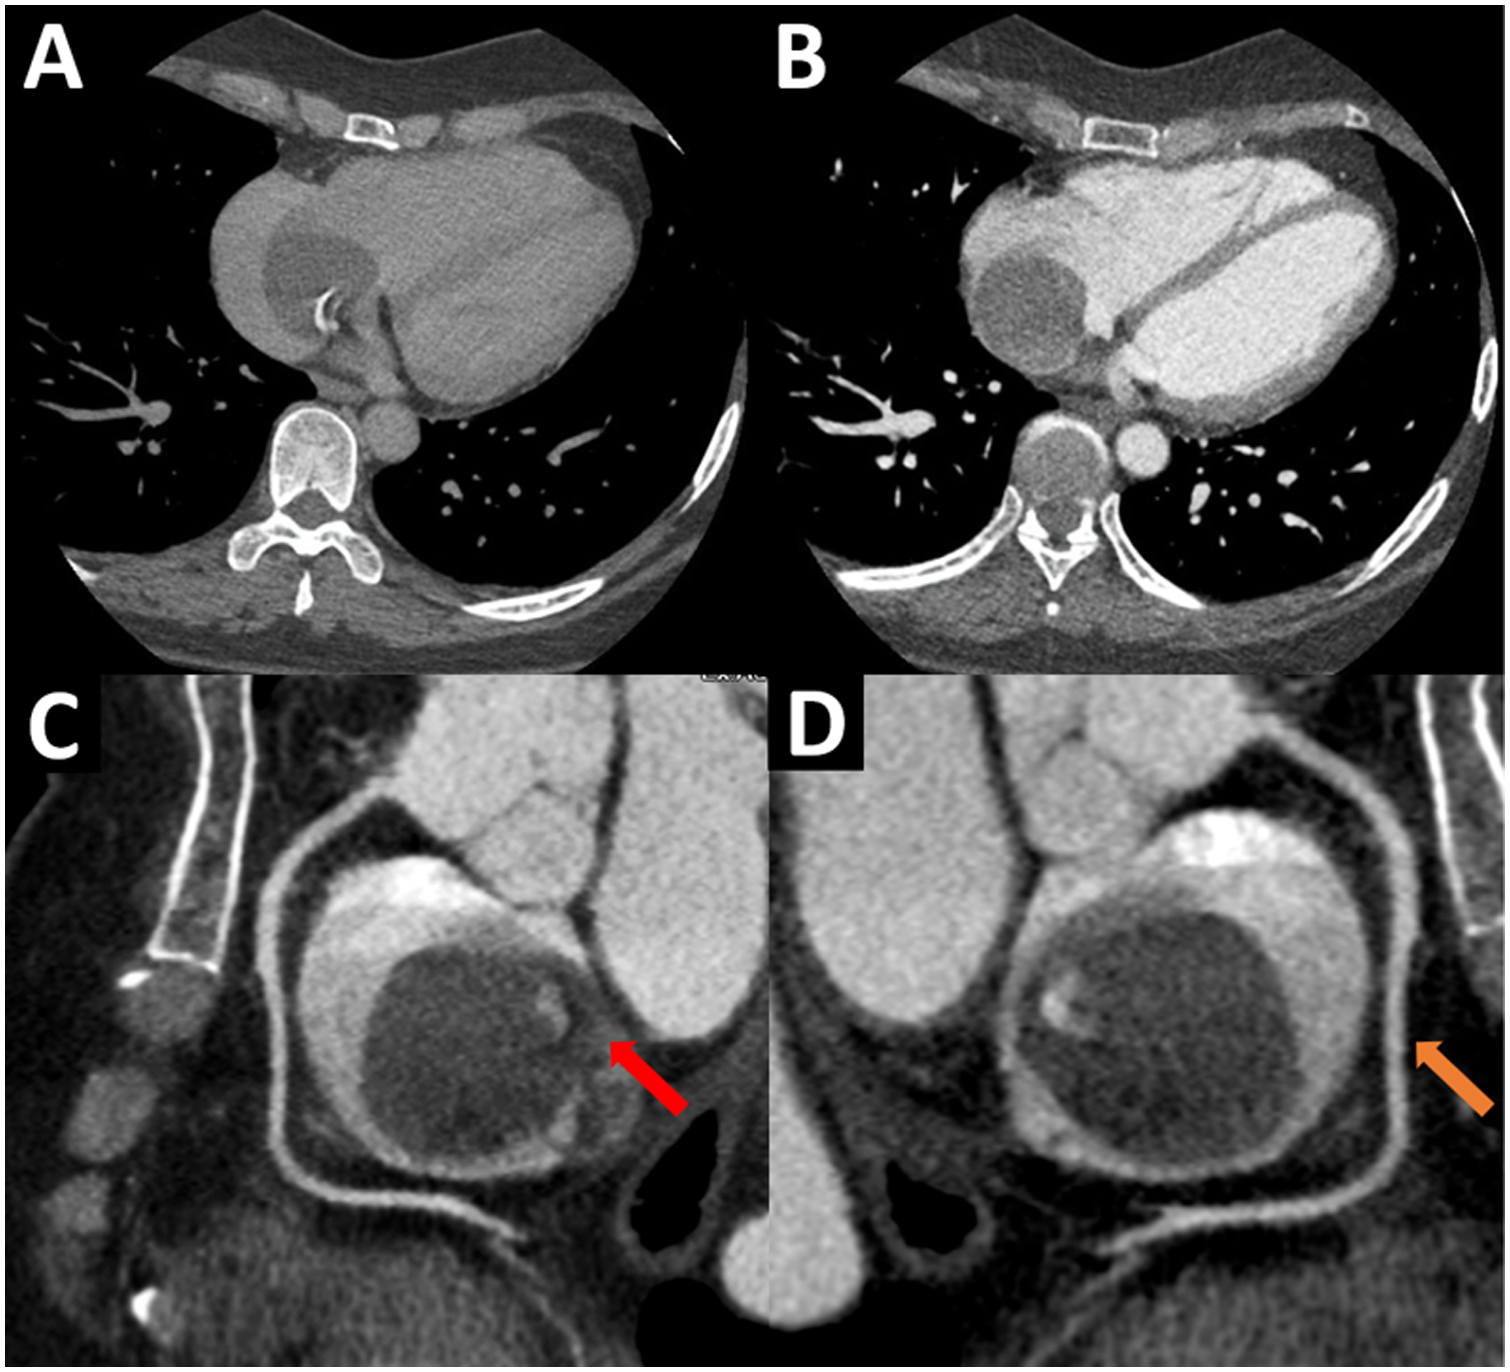

The TEE showed a homogeneous mass covered by a thin layer, implanted in the mid-low septum, and exhibited pendulum movement (Figure 1C, Supplementary Video S3). Furthermore, the previous dimensions were confirmed and no signs suggestive of vascularization were found. Given these findings, the diagnosis work-up was complemented with an ECG-gated CTA, displaying an ovoid, mobile mass of 35 mm in diameter with homogeneous content and calcified areas with a 12-mm pedicle adhered to the lower atrial septum near the coronary sinus ostium (Figure 2).

Figure 2

(A,B) ECG-gated CTA, four-chamber view. A mobile, round, homogenous mass is seen adhered to the right lower interatrial septum. (C,D) ECG-gated CTA, sagittal views of the right atrium. A homogeneous, non-contrast-enhancing mass with calcified areas and defined edges is seen in the right atrium. Note the 12 mm pedicle (red arrow) that attaches it to the interatrial septum, near the fossa ovalis. Likewise, the right coronary artery (orange arrow) is seen, which does not provide collateral to the mass. ECG, electrocardiogram; CTA, computed tomography angiography.

ECG-gated CTA reported a homogeneous mass with calcified areas and defined edges, mobile, without contrast-enhancing or infiltration. Also, it excluded the presence of additional intra-cardiac masses, contributing to better surgical planning (37). Cardiac MRI is an important technique to define contrast uptake in masses. In particular, hematic cysts do not capture medium contrast, because they are not vascularized, unlike a malignant neoplasm (9). Due to the cystic structure, hydatid disease must be ruled out through specific MRI sequences that differentiate it from the hematic cyst. In the former the T1 signal is hypointense and T2 signal hyperintense, while in the latter the T1 and T2 signals are isointense (11). Despite the usefulness of cardiac MRI for the differential diagnosis of cardiac masses, it was not performed in our patient because the magnetic resonator was inoperative during that period; likewise, surgical resection of the cyst had already been decided by the Heart Team based on ultrasound and tomographic features.